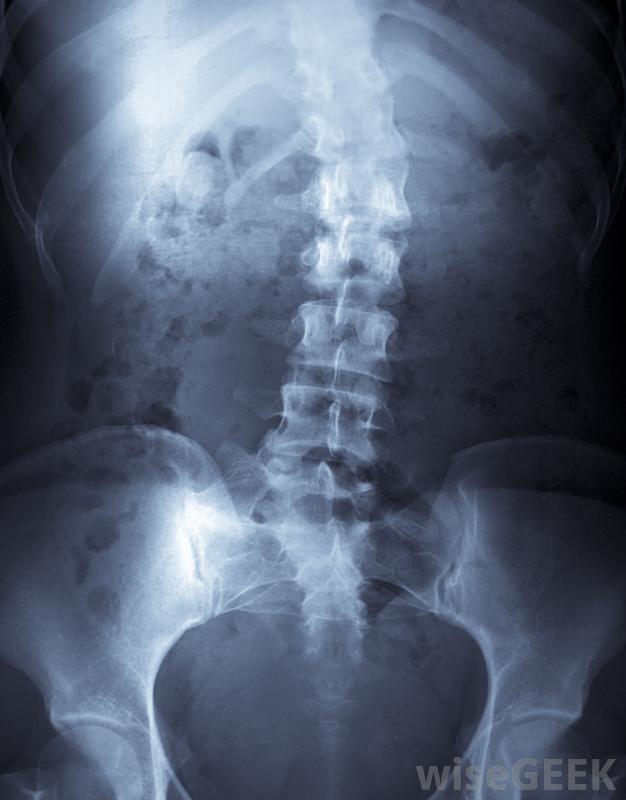

矫形器支架可用于治疗脊柱侧凸,即脊柱的异常弯曲。矫形器支架可以用来帮助支撑脆弱的关节,如脚踝、膝盖或肘部。这些装置也可以帮助矫正或改善运动,包括人的步态,或者它们可以防止受伤或减轻疼痛。有些矫正器,如某些脊柱侧凸矫正器,为了达到预期的效果,每天只需佩戴特定的时间。其他类型的矫正器在需要矫正时都会佩戴,例如为了使病人能够行走而佩戴的矫形器支具,医生也可以通过改变身体的排列方式来减轻神经的挤压和相关的疼痛